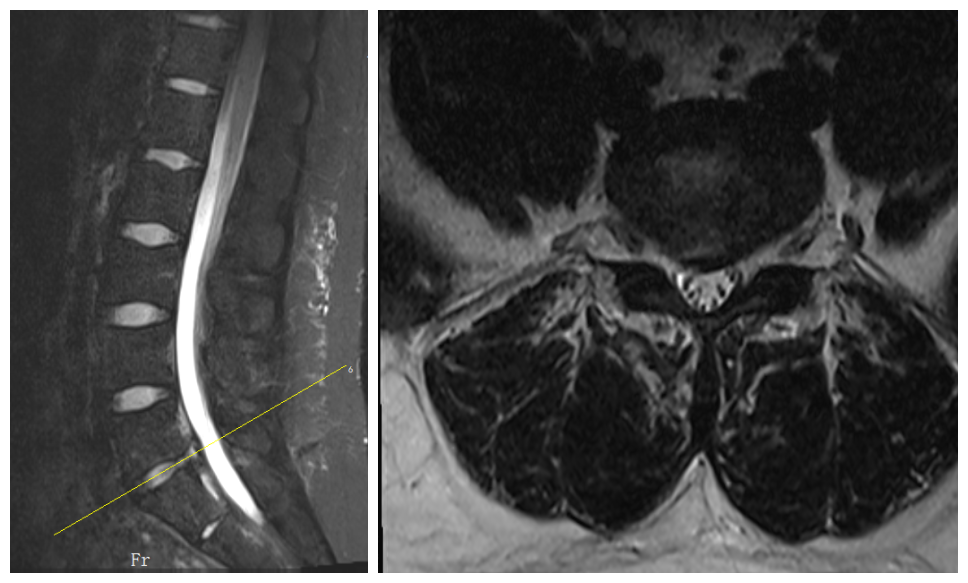

入院检查腰椎磁共振

术后腰椎磁共振